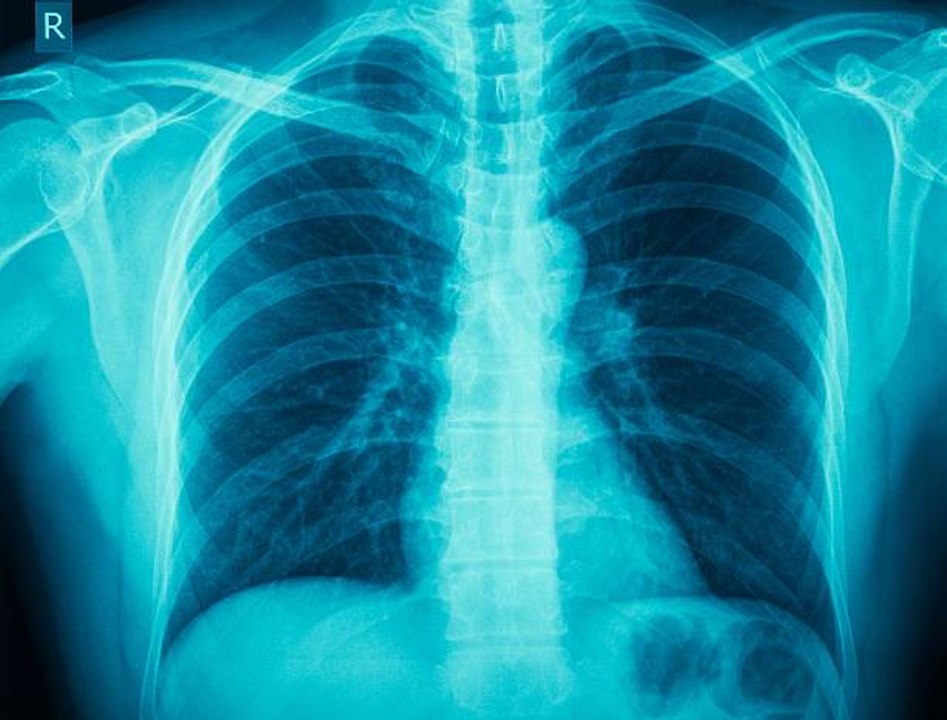

This X-Ray history and education film is informative and engaging for lovers of science. The film begins by touching upon the invention of X-Rays. The discovery of the X-Ray by Wilhelm Conrad Roentgen in 1895 was a unique one that was not fully understood or capitalized on until years later. X-Rays are unique in that the rays can’t be seen but its effects can be made visible. The recording of these X-rays onto film is known as radiography. Spectacular footage of bones moving behind X-rays (without any radiation protection!) are shown in all their glory. This great discovery has led to man advancements in both medicine and industry improving not only the lives of patients and doctors but of businessmen as well, and this film documents it all beautifully.